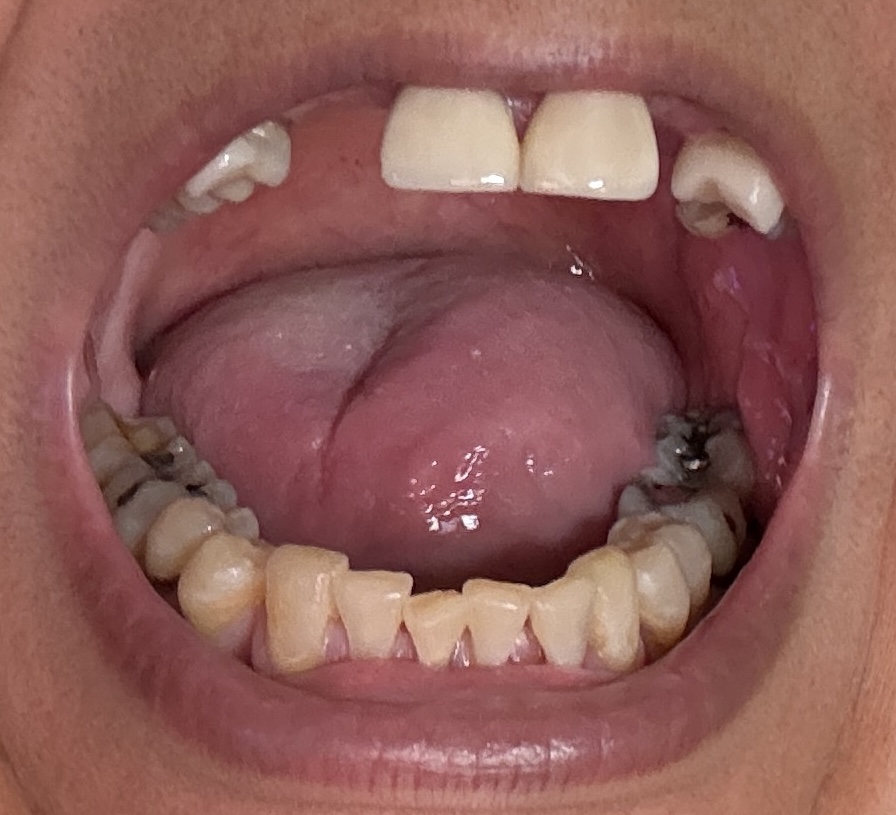

Dental Auction No. 11561: Several extractions and All-on-4 Top and bottom arches

12,13,14 have had root canals in past and now have quite a bit movement. 2-5 have all had root canals in past and now the crowns are breaking down.

Overall information (lower arch)

Overall, all of my gums have receded and most of the bottom teeth are exposed w/ some roots and there are many cavities.